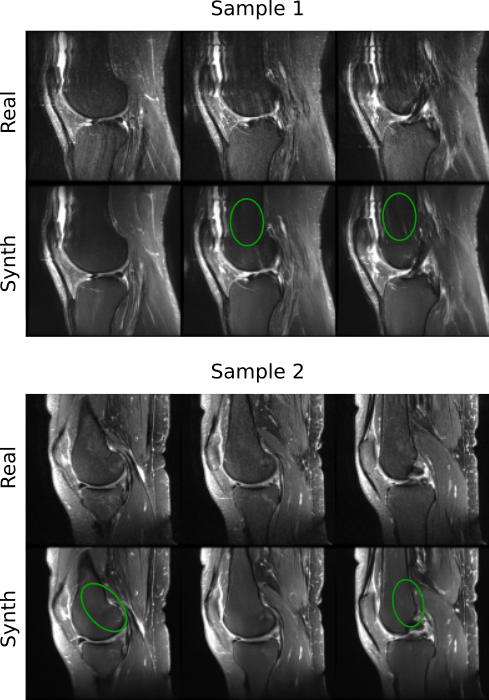

Refer to caption

Figure 6: Representative cross sections of real (Real) and copies (MedDiff, MONAI) detected in the fastMRI datasets. Copies show a high resemblance to the corresponding real samples. MedDiff-synthesized images contain severe artifacts and only share global structures with the corresponding real images.

In fastMRI dataset, (24.8, 30.8) % of the training data were memorized in (MedDiff, MONAI), and (37.3, 51.0) % of the synthetically generated samples were identified as patient data copies in (MedDiff, MONAI). Fig. 6 shows copies that were detected in both MedDiff and MONAI along with the closest training samples. MedDiff-synthesized images contained severe artifacts and were unable to capture low-level structural details. MONAI-synthesized images, on the other hand, had a lower noise level but were slightly blurry.